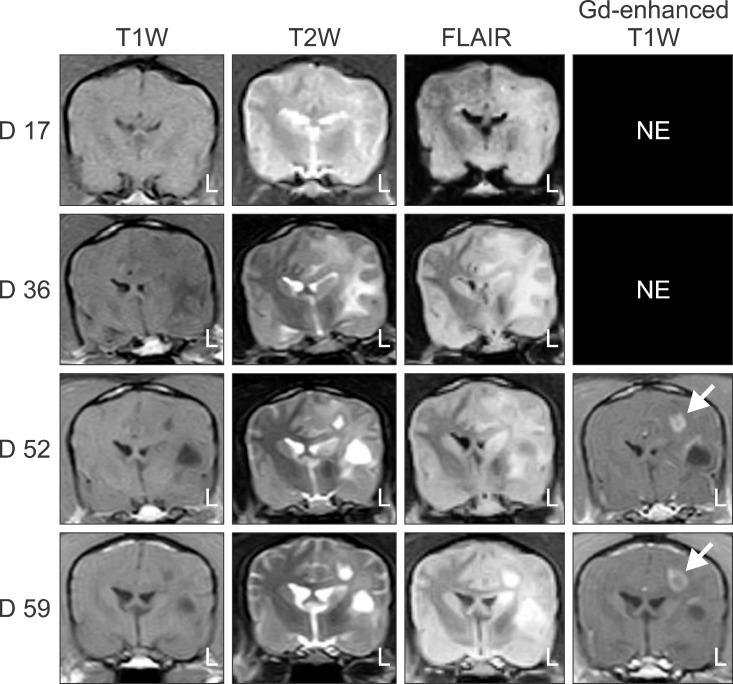

In the present study, the use of dogs with experimental autoimmune encephalomyelitis (EAE) as a disease model for necrotizing encephalitis (NE) was assessed. Twelve healthy dogs were included in this study. Canine forebrain tissues (8 g), including white and grey matter, were homogenized with 4 mL of phosphate-buffered saline for 5 min in an ice bath. The suspension was emulsified with the same volume of Freund's complete adjuvant containing 1 mg/mL of killed Mycobacterium tuberculosis H37Ra. Under sedation, each dog was injected subcutaneously with canine brain homogenate at four sites: two in the inguinal and two in the axillary regions. A second injection (booster) was administered to all the dogs using the same procedure 7 days after the first injection. Clinical assessment, magnetic resonance imaging, cerebrospinal fluid analyses, necropsies, and histopathological and immunohistochemical examinations were performed for the dogs with EAE. Out of the 12 animals, seven (58%) developed clinically manifest EAE at various times after immunization. Characteristics of canine EAE models were very similar to canine NE, suggesting that canine EAE can be a disease model for NE in dogs.